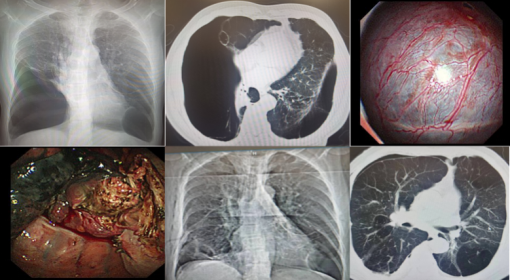

图3.难治性气胸:内科胸腔镜下松解胸腔粘连,消融肺大疱并封堵破口

图5.内科胸腔镜下对恶性胸腔积液患者进行局部消融治疗